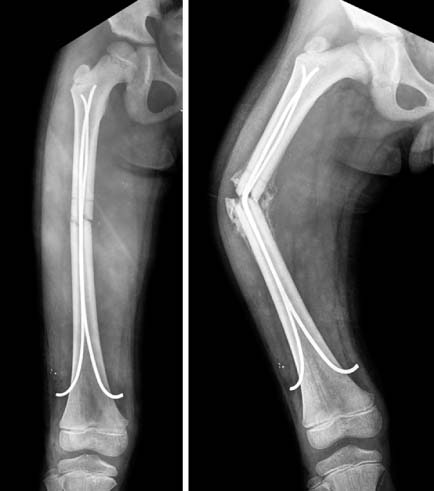

Fig. 5

These are the sequence of operatingprocedure in the suggested patient of Fig. 1. After the temporary reduction of femoral fracture with flexible nails, the plate was introduced through the submuscular tunnel. Then, the locking screws were fixed at the proximal and distal sides of the plate. The fracture site was not open to preserve the biology. The flexible nail makes an easier reduction of fracture, which facilitates the minimally invasive plate osteosynthesis (MIPO) procedure.

Fig. 6

In postoperative films (left), a satisfactory reduction was achieved. The patient had a solid union, on 1 year follow-up films (right).